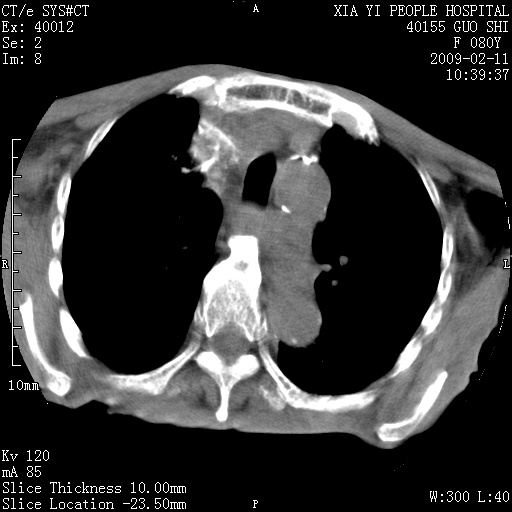

以下是引用随光逐影在2009-2-16 16:34:00的发言:[br]1)考虑右前纵隔皮样囊肿。2)双侧少量胸腔积液。

以下是引用zjzjr在2009-2-16 17:30:00的发言:[br]支持囊性畸胎瘤 双侧少量胸腔积液。